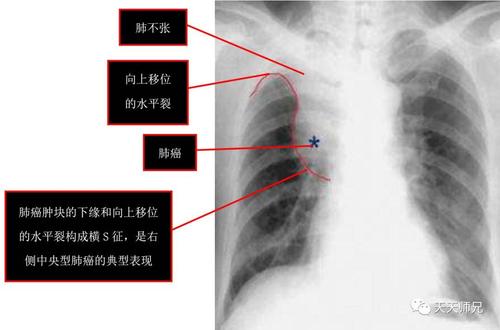

你看这个肺不张的影像是不是导致了水平裂向上移位,并且向上移位的